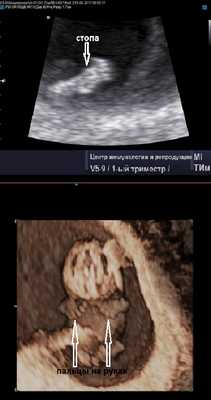

Фото УЗИ плода при беременности 9-10 недель

Продолжается развитие эмбриона. Уже отчётливо видны ручки ножки, а на хорошем аппарате порой удаётся разглядеть даже пальчики на руках и ногах. Частота сердцебиения на этом сроке достигает 170-190 ударов в минуту. Шевеления эмбриона становятся активными, и есть работы, показывающие, что чем активнее ребёнок, тем длиннее будет пуповина (хотя тут может быть и обратная зависимость).